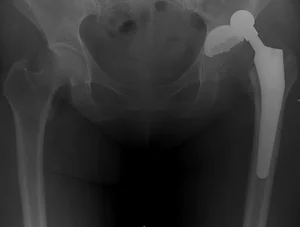

Это ведёт к децентрации головки эндопротеза (на представленной рентгенограмме видно смещение головки эндопротеза от центра) и нарушению функции конечности.

При таком осложнении требуется повторное оперативное вмешательство с целью замены вкладыша.

Протрузия вертлужной впадины

Это внедрение бедренного компонента протеза (головки) в вертлужную впадину с прободением её стенки и выходом в полость малого таза.

Такое осложнение резко нарушает функцию сустава (делает её фактически невозможной), а также чревато повреждением органов малого таза.